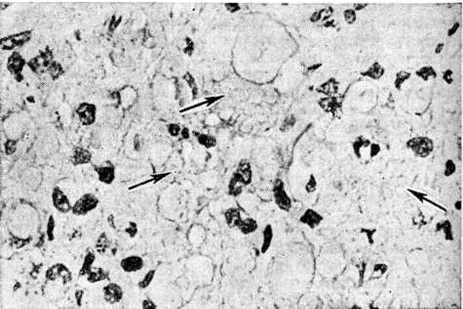

Гистологически лепроматозный тип характеризуется лепроматозной гранулемой кожи, которая представляет инфильтрат, расположенный в сетчатом слое, отделённый от эпидермиса непоражённой зоной коллагеновой ткани. Основными клеточными элементами лепроматозной гранулемы являются лепрозные клетки; кроме того, наблюдаются отдельные плазматические, лимфоидные клетки, единичные фибробласты, многоядерные пенистые клетки (цветной рисунок 1—6). Лепрозные клетки относятся к макрофагам, характеризуются бледным ядром и «пенистой» цитоплазмой (рисунок 5) за счёт содержания липидов. Лепрозный макрофаг на ранних стадиях содержит жирные кислоты, фосфолипиды, ненасыщенные липиды; на стадии развития процесса преобладают нейтральные жиры и кислотные липиды. Большинство исследователей считает, что основная масса липидов представляет собой продукт метаболизма и распада микобактерий Лепра. Наиболее характерная особенность лепрозного макрофага — нахождение и размножение в нем большого количества микобактерий Лепра, то есть явление незавершённого фагоцитоза (смотри полный свод знаний). В цитоплазме лепрозной клетки выявляется высокий уровень окислительно-восстановительных ферментов, кислой фосфатазы, неспецифической эстеразы и не обнаруживается активность липазы. Для гистологический картины LL характерно также наличие капилляров со значительным сужением их просвета за счёт пролиферации и набухания эндотелиальных клеток, содержащих большое количество микобактерий типа «глоби». Кожные нервы пронизаны инфильтратами из микробосодержащих клеток (цветной рисунок 7 и 10). Микобактерии обнаруживаются также в клетках эндоневрия. В лепроматозных поражениях большой давности отмечается частичное или полное разрушение придатков кожи (фолликулов волос, сальных и потовых желёз).

Рис. 5. | ||

Рис. 7. | ||

Рис. 8. | ||